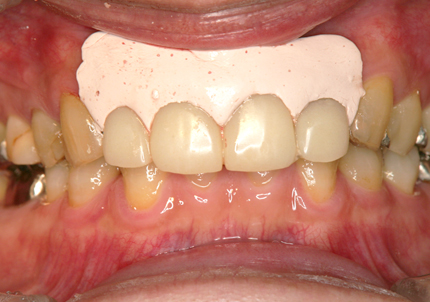

21.ジルコニアブリッジ試適(2020年12月)

22.最終補綴物完成・装着口腔内写真(2021年1月)